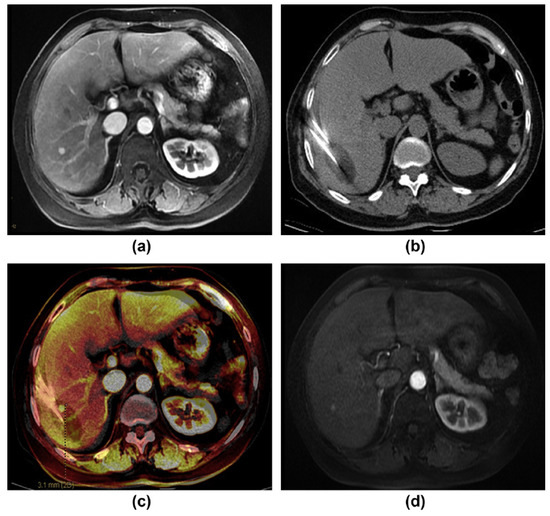

- Chen, C.; Xu, L.; Wang, Y.; Wang, Y.; Li, G.; Huang, H.; Wang, B.; Li, W.; He, X. Assessment of the cryoablation margin using MRI–CT fusion imaging in hepatic malignancies. Clin. Radiol. 2019, 74. [Google Scholar] [CrossRef]